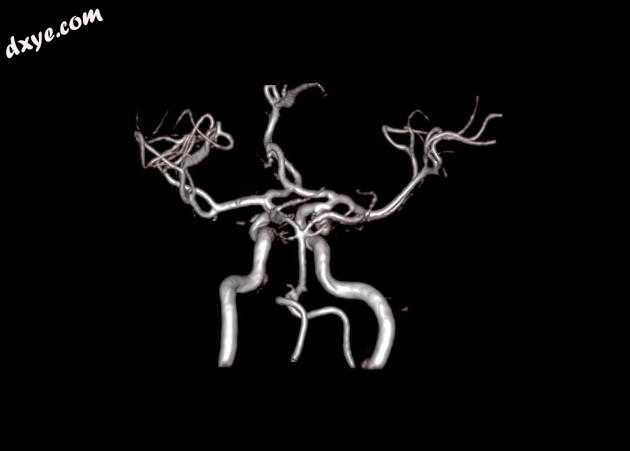

MRA 3D-TOF

MRI 序列显示右侧颈内动脉的部分血栓囊状动脉瘤位于 C6/7 节段的交界处,大小为 11 x 7 毫米,颈部为 2.5 毫米,压迫动眼神经 (III) 的相邻节段,在 T1 上清晰可见和 FIESTA 序列。

位于 C6/7 交界处的右侧颈内动脉部分血栓囊状动脉瘤的 MRI 特征,压迫同侧动眼神经 (III)。